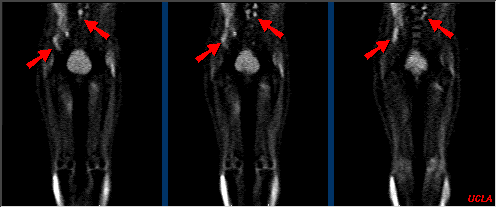

Whole Body FDG-PET

Multiple foci of increased FDG metabolism are evident (arrows). These are most prominent in the right lower quadrant and in the periaortic nodes. Study is highly suspicious for recurrence of disease in these areas.

On follow-up, surgery confirmed the metastatic omental disease and the periaortic nodal involvement. Note that by performing an FDG-PET study prior to surgery, attention can then be focused on the appropriate surgical sites of both the primary tumor and metastases.